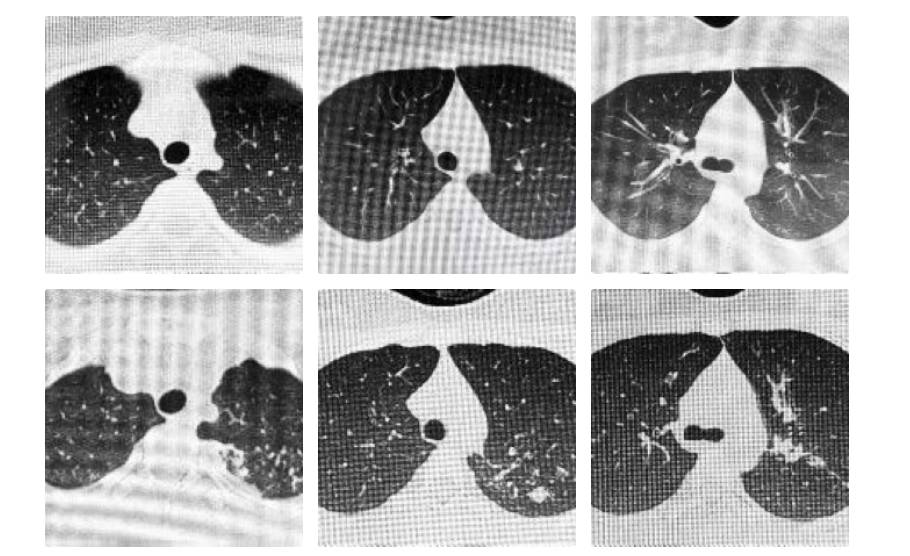

两年前一次学校的结核病筛查中,初中女生阳阳(化名)被测出了“阳性”结果。这本是“潜伏感染”的重要警报,意味着结核菌已潜入体内,但被免疫系统暂时围困。但她和家人并未当回事。两年后当阳阳再次走进诊室,胸部CT片已清晰显示:左上肺出现典型结核病灶,甚至可能已累及支气管,从“潜伏感染”已进展为“活动性肺结核”。值得注意的是,她仍然几乎没有症状。

上排为两年前,下排为两年后